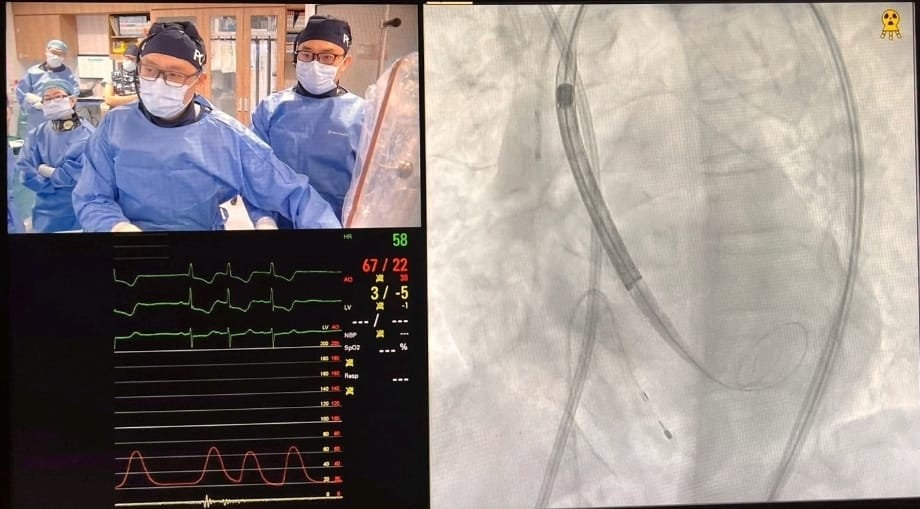

Pushing the frontiers of heart care ❤️ A proud moment for #NUHCS at #AVPlusCONNECT Modern PCI LIVE - Prof Tan Huay Cheem, Senior Advisor, & Dr Christopher Koo, Consultant, successfully performed a complex live heart procedure among 9 global collaborations & 80 live cases. 👏

AICT-AsiaPCR 2025, a major cardiology conference, gathered over 1,000 experts for 2 days of learning. #NUHCS presented 4 complex treatment procedures led by A/Prof Mark Chan, A/Prof Adrian Low, Adj A/Prof Loh Poay Huan, Asst Prof Ivandito Kuntjoro, Dr Gavin Ng & Dr Qian Qi.